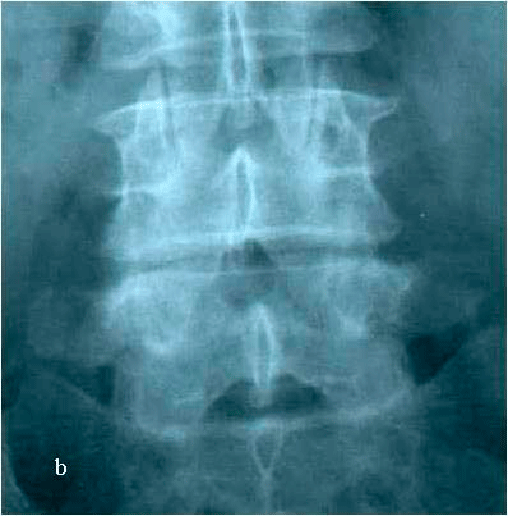

При МРТ и рентгенографии поясничного отдела позвоночника выявляется спондилолизный антеролистез L4 позвонка со стенозированием позвоночного канала на указанном уровне, грыжа мп диска L4-L5 слева. (Рис.7а,б. Рис.8а,б)

Рис. 8а. Рентгенограмма поясничного отдела позвоночника в боковой (а) и прямой (b) проекциях до операции. Стрелкой показано смещение тела L4 позвонка кпереди. Рис. 8b. Рентгенограмма поясничного отдела позвоночника в боковой (а) и прямой (b) проекциях до операции. Стрелкой показано смещение тела L4 позвонка кпереди.

Рис. 8а,b. Рентгенограмма поясничного отдела позвоночника в боковой (а) и прямой (b) проекциях до операции. Стрелкой показано смещение тела L4 позвонка кпереди.